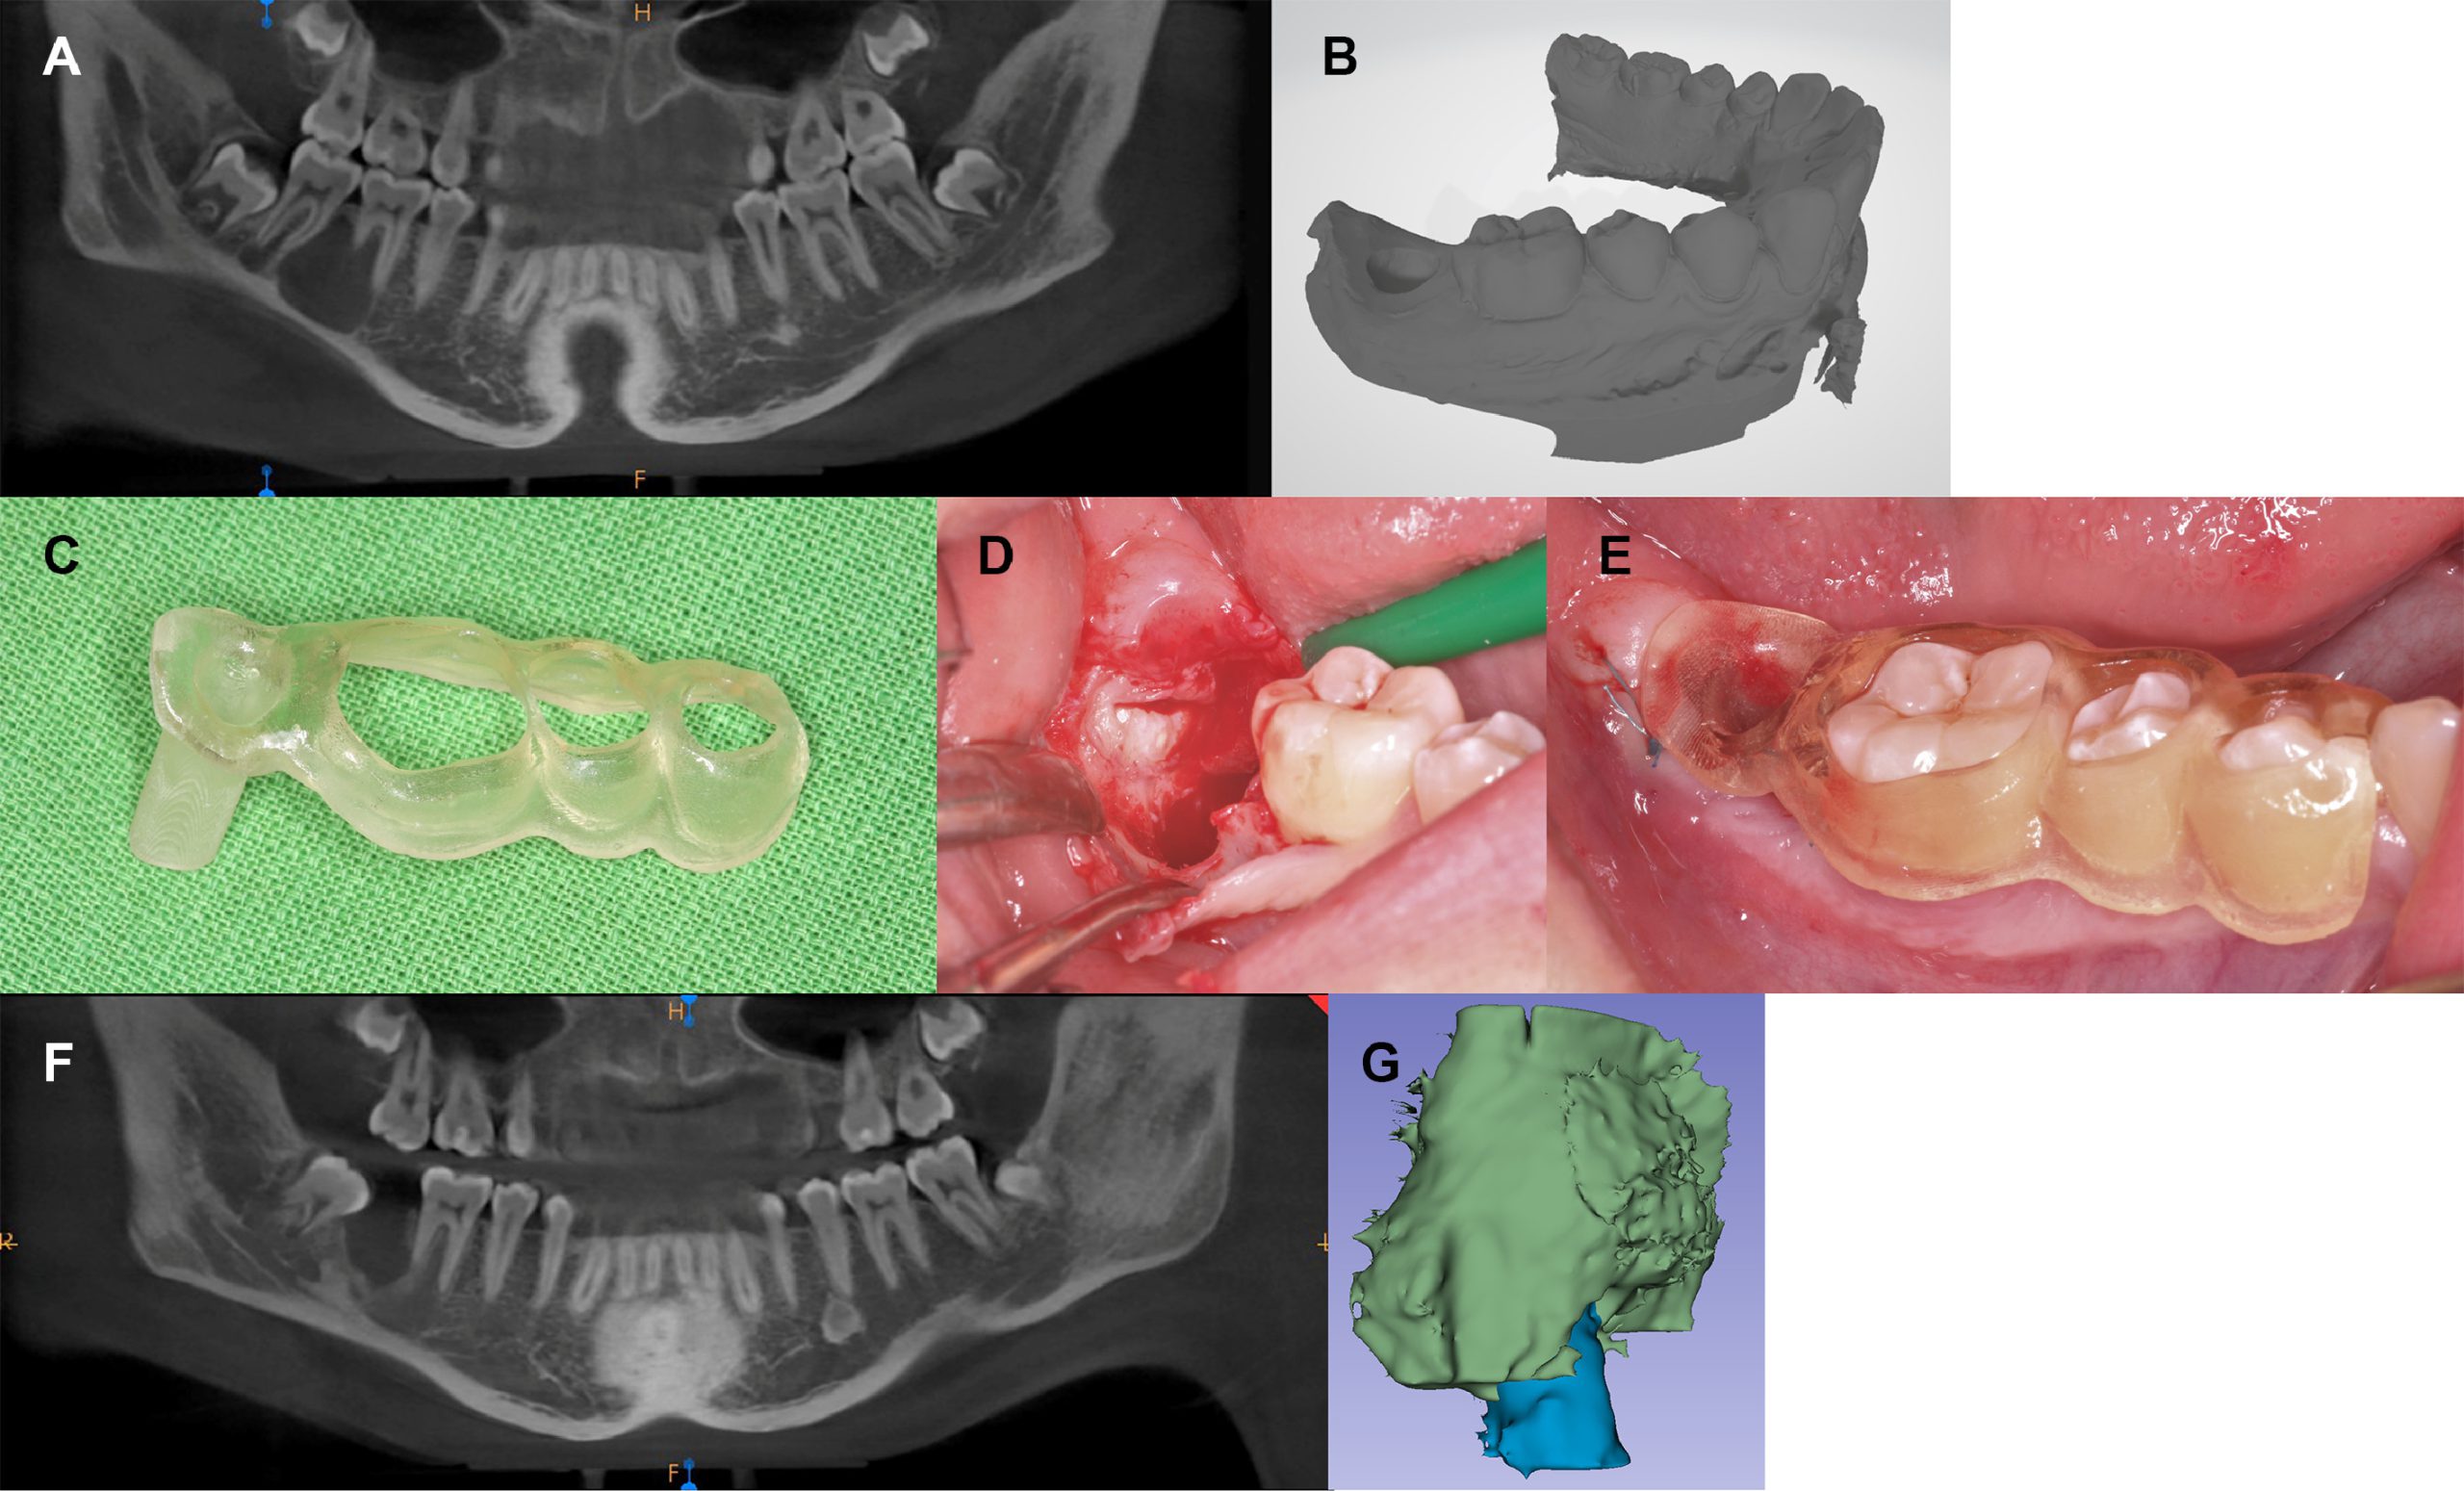

Mở thông nang giảm áp sử dụng lỗ thông kết hợp máng kỹ thuật số

Mở thông nang điều trị nang chân răng hàm dưới

5.4. Mở thông nang kết hợp bóc tách nang thì hai

Sau một thời gian mở thông nang khi lòng nang đã thu nhỏ có thể thực

hiện bóc tách nang mà không gây ảnh hưởng tới các cấu trúc giải phẫu quan trọng có liên quan.